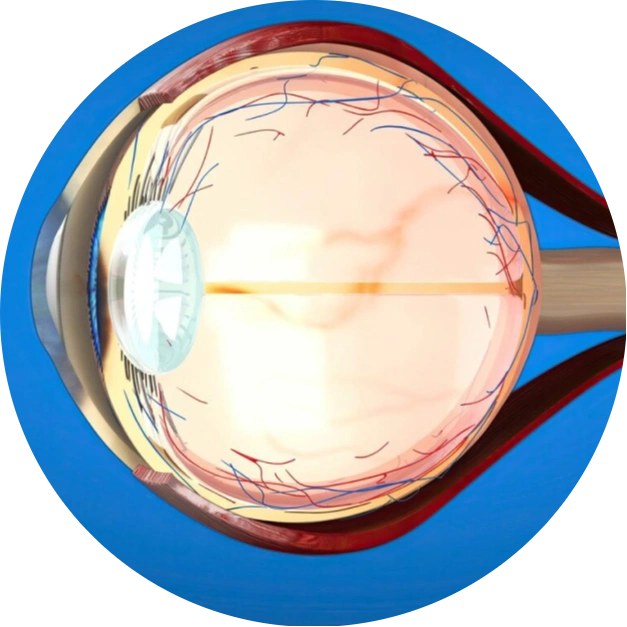

Vitreo-Retina refers to a subspecialty within ophthalmology that focuses on diagnosing and treating conditions affecting the vitreous humor and retina, the innermost layer of the eye. The vitreous is a gel-like substance filling the center of the eye, while the retina is a thin tissue lining the back of the eye, responsible for converting light into signals sent to the brain for vision.

Vitreoretinal diseases are disorders that impact the retina and the vitreous within the eye. The retina, situated at the back of the eye, is responsible for sensing light and transmitting visual information to the brain through the optic nerve. Meanwhile, the vitreous is a transparent gel that occupies the space between the lens at the front of the eye and the retina.